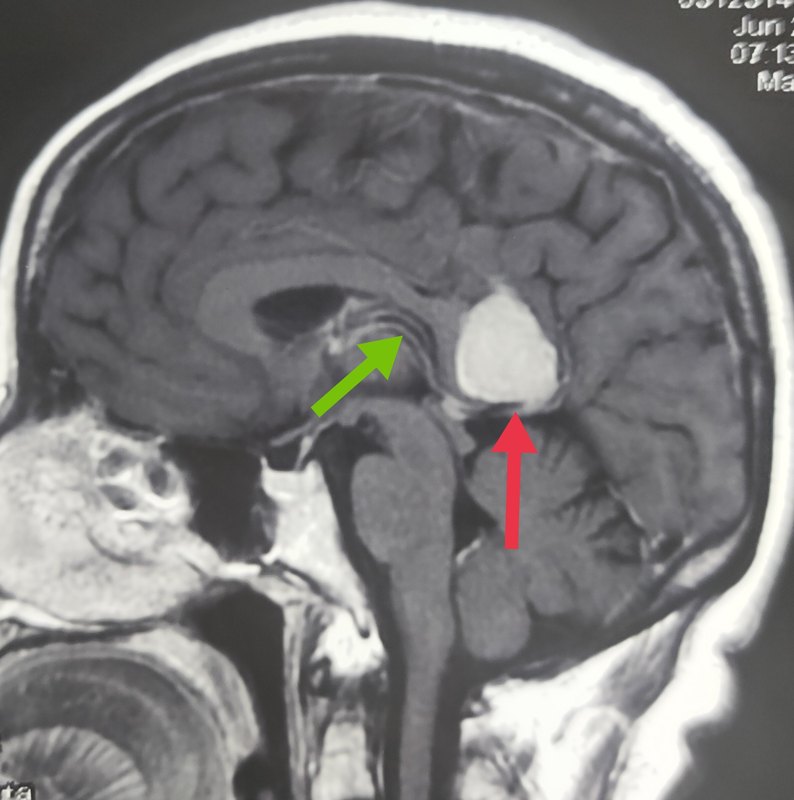

9、2025年4月,北京天坛医院赵继宗院士团队成功为86岁患者切除65cm巨大脑膜瘤,刷新高龄神经外科手术纪录,为同类病例治疗提供了重要参考图1 赵继宗院士为患者做手术一手术背景与患者情况肿瘤特征患者秦女士的脑膜瘤直径达65cm,约占大脑四分之一体积,核磁影像显示其白色阴影几乎占据颅内四分之一空间肿瘤从大脑凸面延伸至中颅凹底,紧贴。

13、母亲在北京天坛医院治疗脑膜瘤的全过程如下确诊阶段2020年9月,母亲因车祸接受脑部核磁共振检查,意外发现左侧眼球后方的蝶骨嵴脑膜瘤肿瘤大小24x25x22cm医生指出该位置手术风险高,建议转诊至大医院进一步评估初诊与观察期2020年国庆后,家属陪同母亲前往北京天坛医院就诊神经外科专家认为。